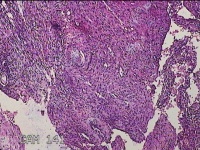

右卵巢囊肿壁

性别

女

年龄

36岁

临床诊断

右卵巢子宫内膜异位囊肿 盆腔炎性疾病后遗症

一般病史

痛经5年,加重3月。

标本名称

大体所见

灰白暗红色囊壁样组织4.5x3.3x0.8cm一堆,表面光滑,因已切开,囊内容物已流失,囊壁厚0.1cm。